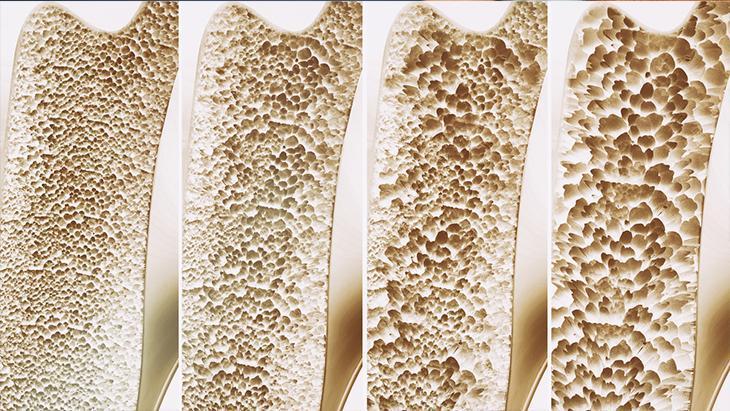

Kemik dokusunda ve kalitesinde bozulma olunca erimenin ortaya çıktığını belirten Dr. İlin, “Osteoporoz kemiklerde kırık riskini artırarak hem yaşam kalitesini düşüren hem de ölümle sonuçlanabilen komplikasyonlara yol açabilen ve kırık oluşana kadar sessiz seyreden bir hastalıktır. Kemik kırılganlığında artış her kadının yaşayacağı bir sorun olarak karşımıza çıkıyor.

Kemiklerin çok dinamik bir organ olduğunu söyleyen Uzm. Dr. İlin, normal kemik dokusunda sürekli ve dengeli bir şekilde yapım ve yıkımın söz konusu olduğunu söyledi. Doğumdan ergenliğe kadar şekillenip büyümeye devam eden kemik kütlesinin, ergenlikte doruğa ulaştığını söyleyen Uzm.Dr. İlin, bu dönemde sahip olunabilinecek güçlü kemik yapısı oranına paralel olarak ilerleyen yaşlarda osteoporoz gelişme riskinin azalacağını dile getirdi.

Dr. Sena İlin, 30 yaşından sonra her iki cinste de yılda ortalama yüzde 0,2-0,5 oranında kemik yoğunluğu kaybının gerçekleşmeye başladığını aktardı.